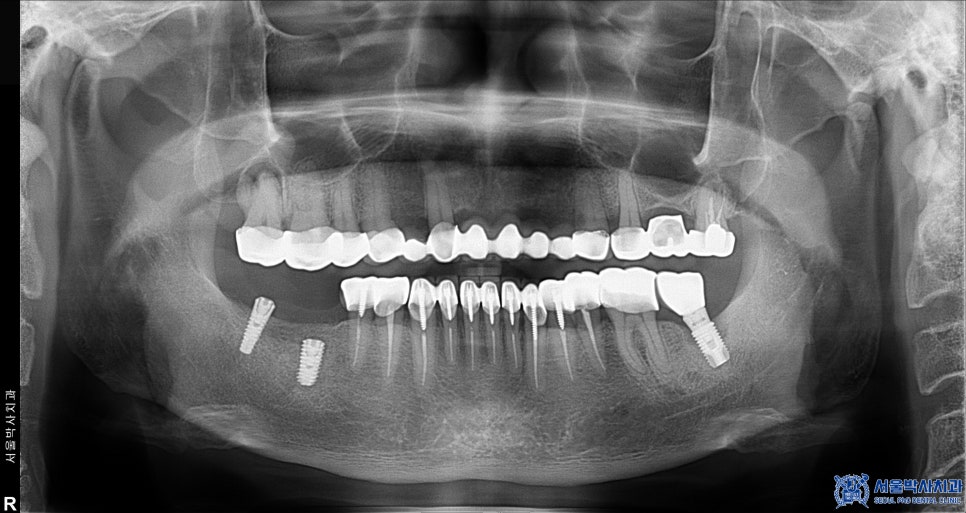

위 환자분께서는 예전에 다른 치과에서

아래쪽 어금니에 임플란트를 하셨었는데,

사용하시던 임플란트가 파절되면서

제대로 기능하지 못해 불편함을 느끼시곤

신흥동치과 서울박사에 내원해 주셨는데요.

오른쪽 아래 기존 임플란트 중 뒤쪽 큰 어금니는

임플란트와 인공 치아를 연결해주는 부분이 파절되었고

앞쪽 큰 어금니 임플란트는 염증으로 인해

상태가 좋지 않았기 때문에

제거 후 재수술을 진행해야 했습니다.